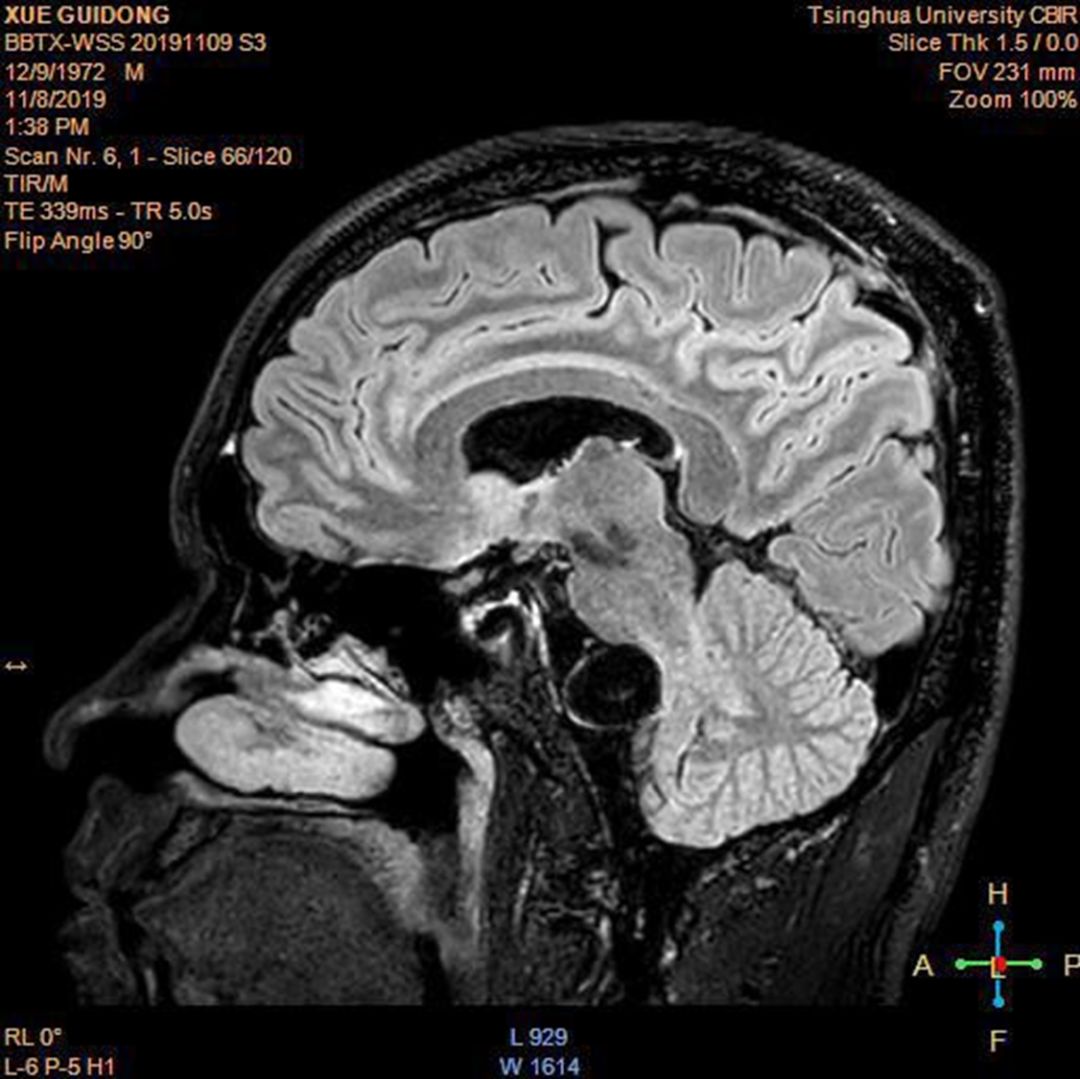

图5 高分辨头颅核磁,脑干受压明显

本例为椎基底结合部动脉瘤,病程缓慢患者无明显症状,但高分辨影像可见脑干受压明显考虑为夹层动脉瘤。对于基底动脉夹层动脉瘤,在以往没有密网支架时,一般采用多个支架辅助弹簧圈栓塞治疗,缺点是复发率高。自从密网支架出现后,其越来越多的被应用于此部位动脉瘤的治疗,但此部位使用密网支架为超适应症(Off-label)应用,所以对于基底动脉瘤应严格把握密网支架的治疗适应症,一般对于此部位稳定的囊状中小型动脉瘤可以进行动态随访观察,如果随访过程中发现动脉瘤不稳定,才考虑予以干预。本次动脉瘤经高分辨磁共振检查为夹层动脉瘤(脑干受压明显),可以考虑密网支架Tubridge辅助弹簧圈栓塞。

患者左侧为优势椎动脉而且开口明显狭窄,为避免术后出血及夹层出现,7F导引导管放在左侧锁骨下动脉近椎动脉开口处(没有进入椎动脉),术中头端柔软且对血管刺激小的Navien中间导管进入椎动脉把对后循环脑血管的影响降到了最低,本例根据精准测量的数据选择4.5 mm*45 mm的Tubridge密网支架释放后,可见密网支架全程贴壁良好,密网支架近端与远端均跨越瘤颈的正常血管段超过6 mm以上,效果满意,左侧撤出Navien中间导管后然后从右侧椎动脉进行动脉瘤弹簧圈栓塞并闭塞右椎动脉末端,保留右侧椎动脉PICA动脉的血流通畅。为减轻巨大夹层动脉瘤术后缺血、缺氧导致的炎症反应,术后给予患者甲强龙80 mg bid,2天,出院后给予口服醋酸泼尼松片10 mg qd,一周。